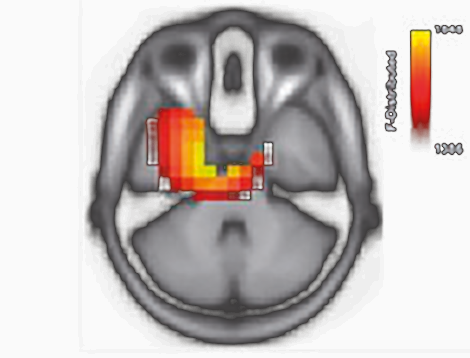

Julia Campbell and Anu Sharma, "Compenstatory changes in cortical resource in adults with